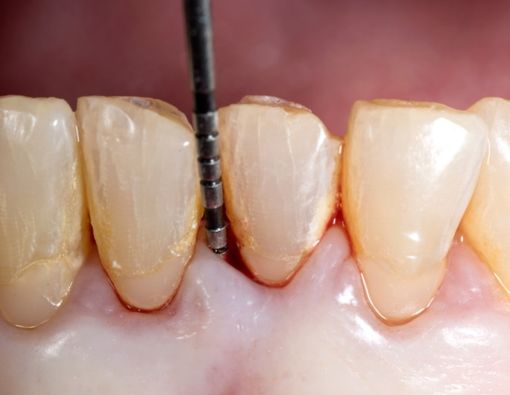

6. Terlihat Ada Lapisan Putih di Leher Gigi

Gigi umumnya berwarna putih kekuningan. Jika gigi berlubang, maka gigi biasanya akan berwarna kehitaman.

Sementara itu, bila kamu melihat warna putih pada perbatasan gigi dan gusi, bisa jadi itu merupakan sisa makanan yang menempel.

Nah, apabila pada lokasi yang sama terlihat ada sesuatu yang berwarna kekuningan seperti gigi, kamu patut mencurigai adanya karang gigi.

Ingat, karang gigi dapat mencetuskan periodontitis. Jadi, pastikan kamu mencegah gangguan ini dengan mengamati adanya karang pada gigi.